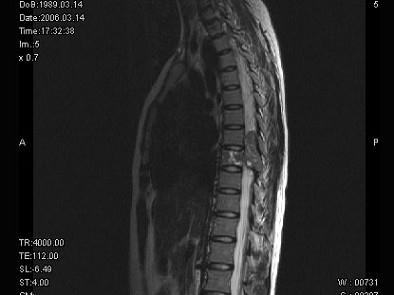

问题 女,18岁,腰以下麻木、双下肢无力,行走困难。PE:双下肢肌力IV+级,肌张力高,腱反射活跃,T以下痛觉消失,深感觉减退,请根据所提供图像,选择最可能的诊断 ( )

选项 A、脊膜瘤 B、淋巴瘤 C、骨母细胞瘤 D、骨巨细胞瘤 E、神经鞘瘤

答案 D